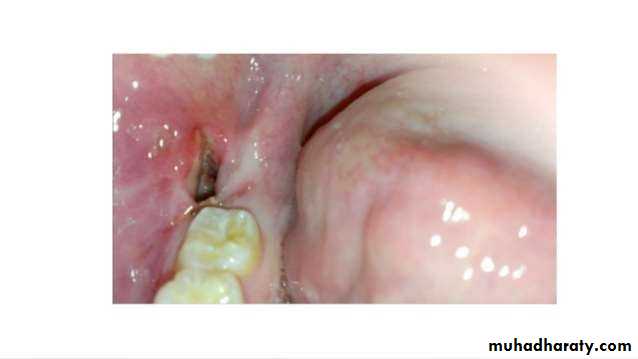

• A descriptive definition that could be used universally as a standardized definition for dry socket :

• post operative pain in and around the extraction site , which increases in

• Severity at any time between 1 and 3 days after the extraction

• Accompanied by a partially or totally disintegrated blood clot within

• the alveolar socket with or without halitosis.

• The denuded alveolar bare bone may be painful and tender.